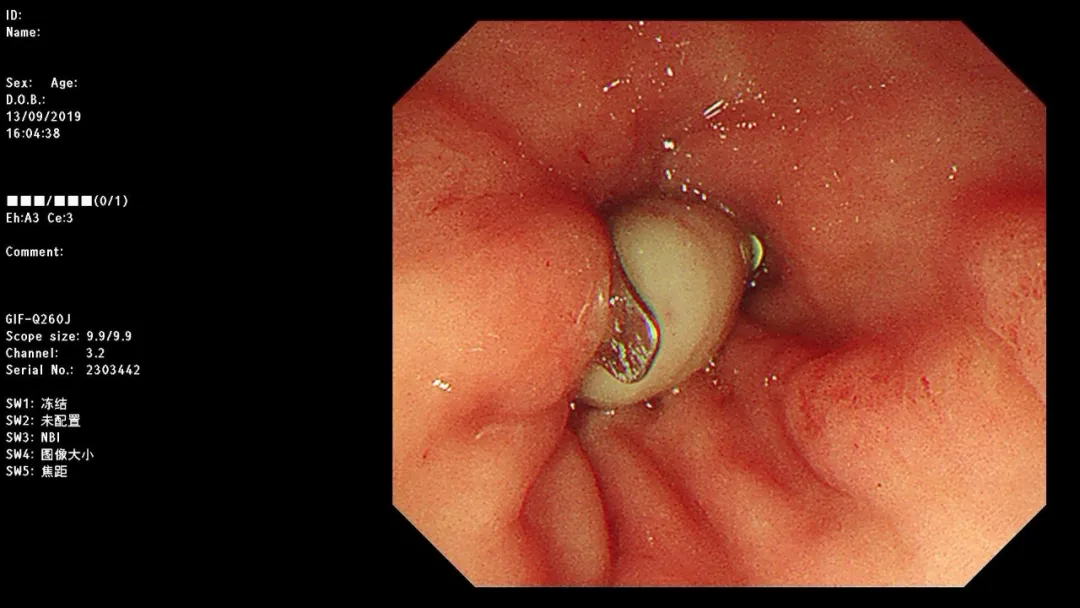

急诊胃镜示:小弯近胃窦侧活动性出血灶活动性渗血,采用OTSC吻合夹予以夹闭治疗,检查诊断:胃窦杜氏溃疡并出血OTSC吻合夹夹闭止血治疗术。